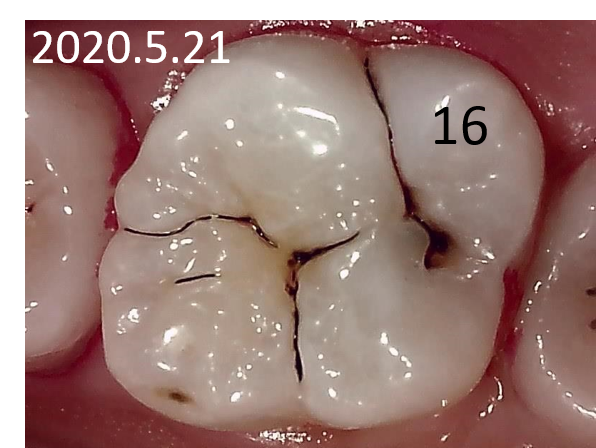

症例① 上顎大臼歯 小窩や裂溝の虫歯 20歳女性

※小窩や裂溝:歯の咬み合せ面にある複雑なくぼみや溝のこと

初診時口腔内写真 |

![]() 初診時レントゲン写真 |

症例①②

主訴 |

正しい口腔ケアを知り、健康的になりたい。 |

診断 |

上下大臼歯の初期虫歯 |

治療 |

経過観察 |

期間 |

経過観察中 |

費用 |

0円 |

治療リスク |

虫歯進行の可能性 |